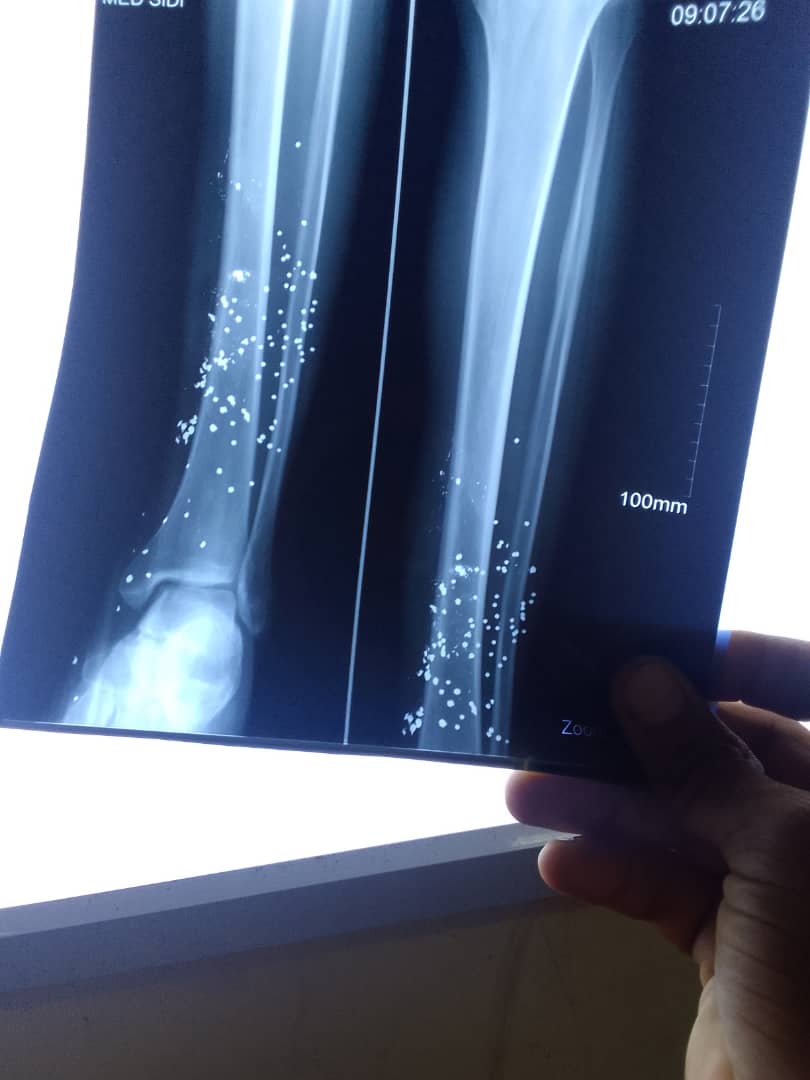

وحسب مصدر خاص ل (لمسيله ميديا) فإن عصابة من اللصوص من اصحاب السوابق حاولوا ارغام صاحب محل تجاري يقع بالقرب من  مسجد الرسول في مقاطعة الميناء بجانب "شتادو" على فتحه ليلا،فقام باطلاق النار عليهم من بندقيته(بوفلكه) فأصاب احدهم في الساق  فلاذوا بالفرار قبل ان يعودوا أدراجهم لأخذ رفيقهم الى المستشفى مدعيين انه اصيب بواسطة آلة حادة، لكن فريق المداومة الطبية اشترط استدعاء عناصر الشرطة لتتكشف الحقيقة.